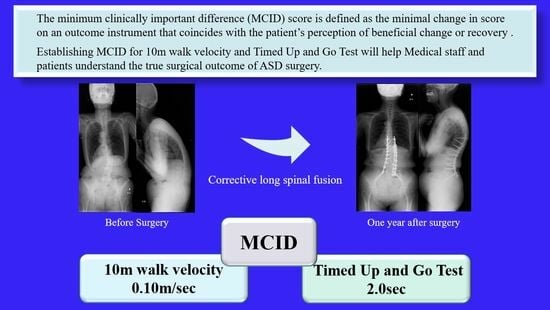

Minimal Clinically Important Differences in Gait and Balance Ability in Patients Who Underwent Corrective Long Spinal Fusion for Adult Spinal Deformity

Abstract

:1. Introduction

2.2. Outcome Assessment

2.2.1. Ten Meter Walk Velocity

2.2.2. Timed Up-and-Go Test (TUG)

5. Conclusions